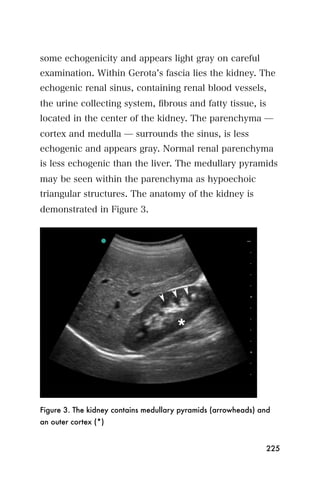

metastases that contain large amounts of mucin tend to

be echogenic. Similarly, vascular lesions can be

echogenic due to numerous interfaces arising from

vessels. Fewer echogenic metastases are encountered in

processes that are highly cellular but lack internal

interfaces.

Large metastases that outgrow their blood supply can be

heterogeneous with areas of necrosis and cystic change,

making them difficult to distinguish from abscesses. A

common type of liver metastases is the bull s eye or

target lesion, and these are commonly associated with

adenocarcinomas of breast or gastrointestinal origin.

The central area of echogenicity probably arises from